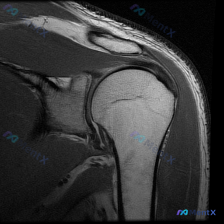

冈上肌腱撕裂 vs 盂唇病变?这份肩关节MRI影像的诊断陷阱

看到一份肩关节MRI影像分析报告,有意思的是报告里的客观发现和用户的关注点不太一样。先放影像的基本信息:

- 检查类型:肩关节MRI冠状位T2序列

- 用户原问题:What can be observed in this image?(Labral pathology)

- 影像报告关键词:冈上肌腱撕裂、盂唇信号尚可

大家第一眼看到这份报告的描述,最关注的会是什么?对于“冈上肌腱撕裂”和“盂唇病变”这两个方向,你更倾向于哪个?